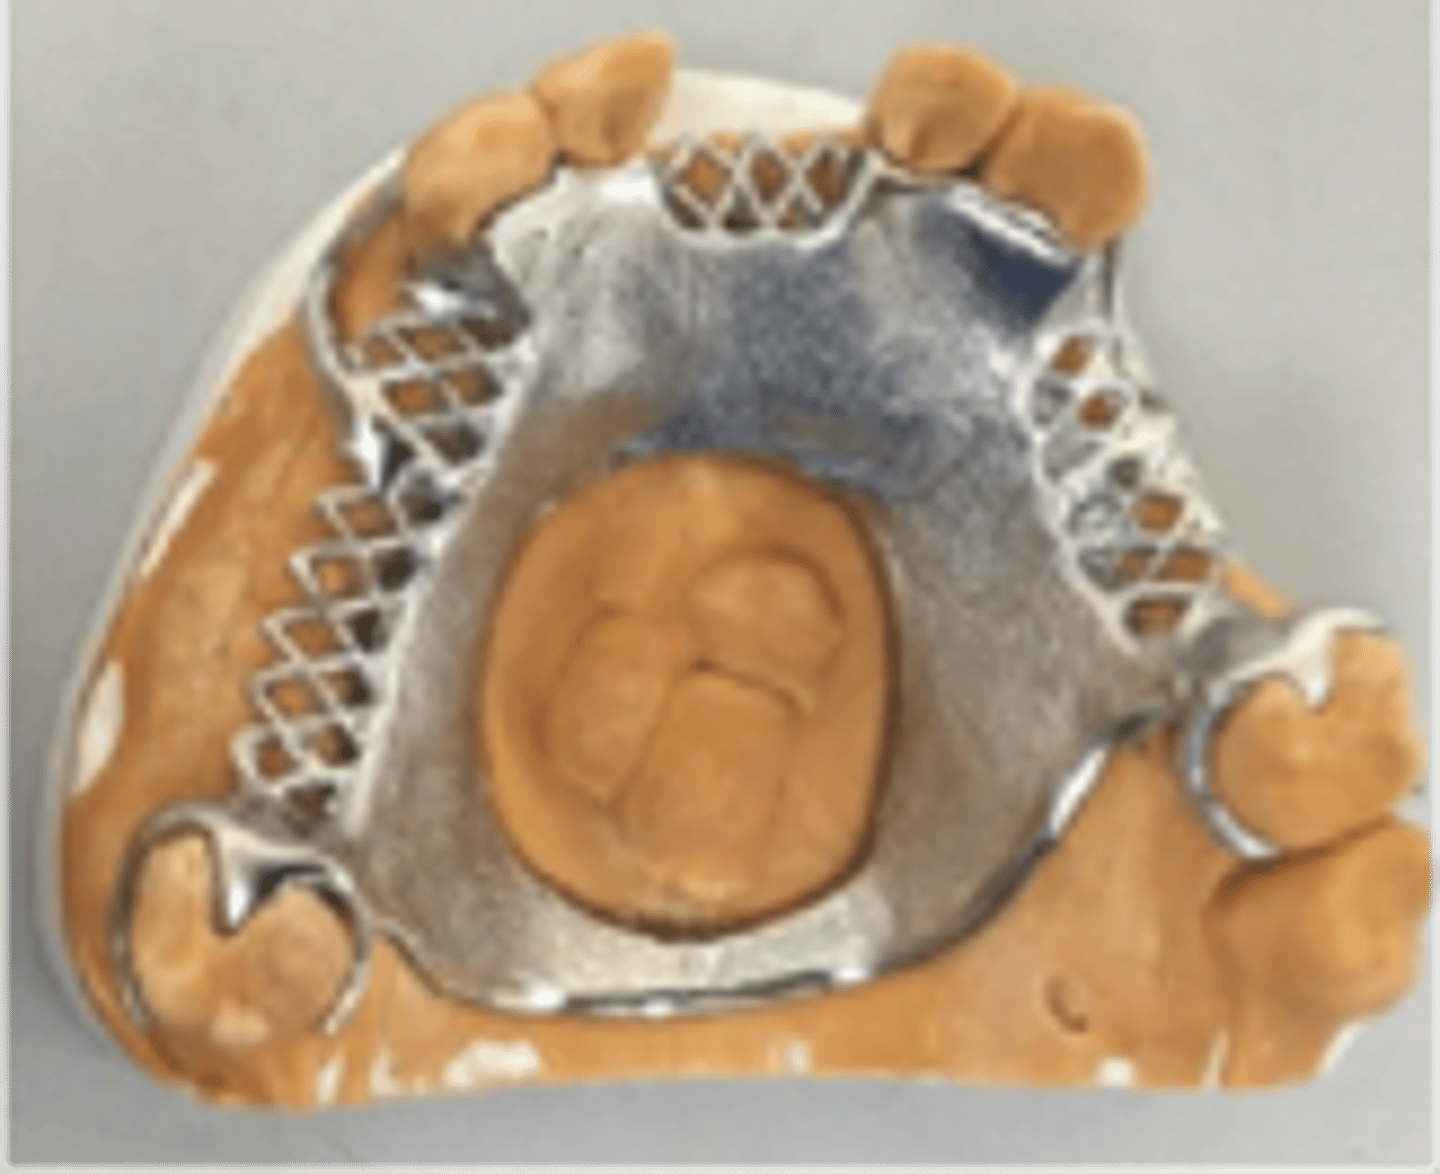

Acrylic Retention area

Since acrylic and metal do not bond, mechanical retention is required: Lattice, mesh, post, loop, beading

relief

mesh and lattice are made with ______ underneath to allow acrylic to wrap around metal completely

Beading and loops

hold denture tooth "veneer" (occluding surface is part of metal framework)

Tissue stop

small projection of metal at the distal end of an extension base framework that contacts the cast and prevents downward movement of the acrylic retention area during the processing of the RPD for delivery